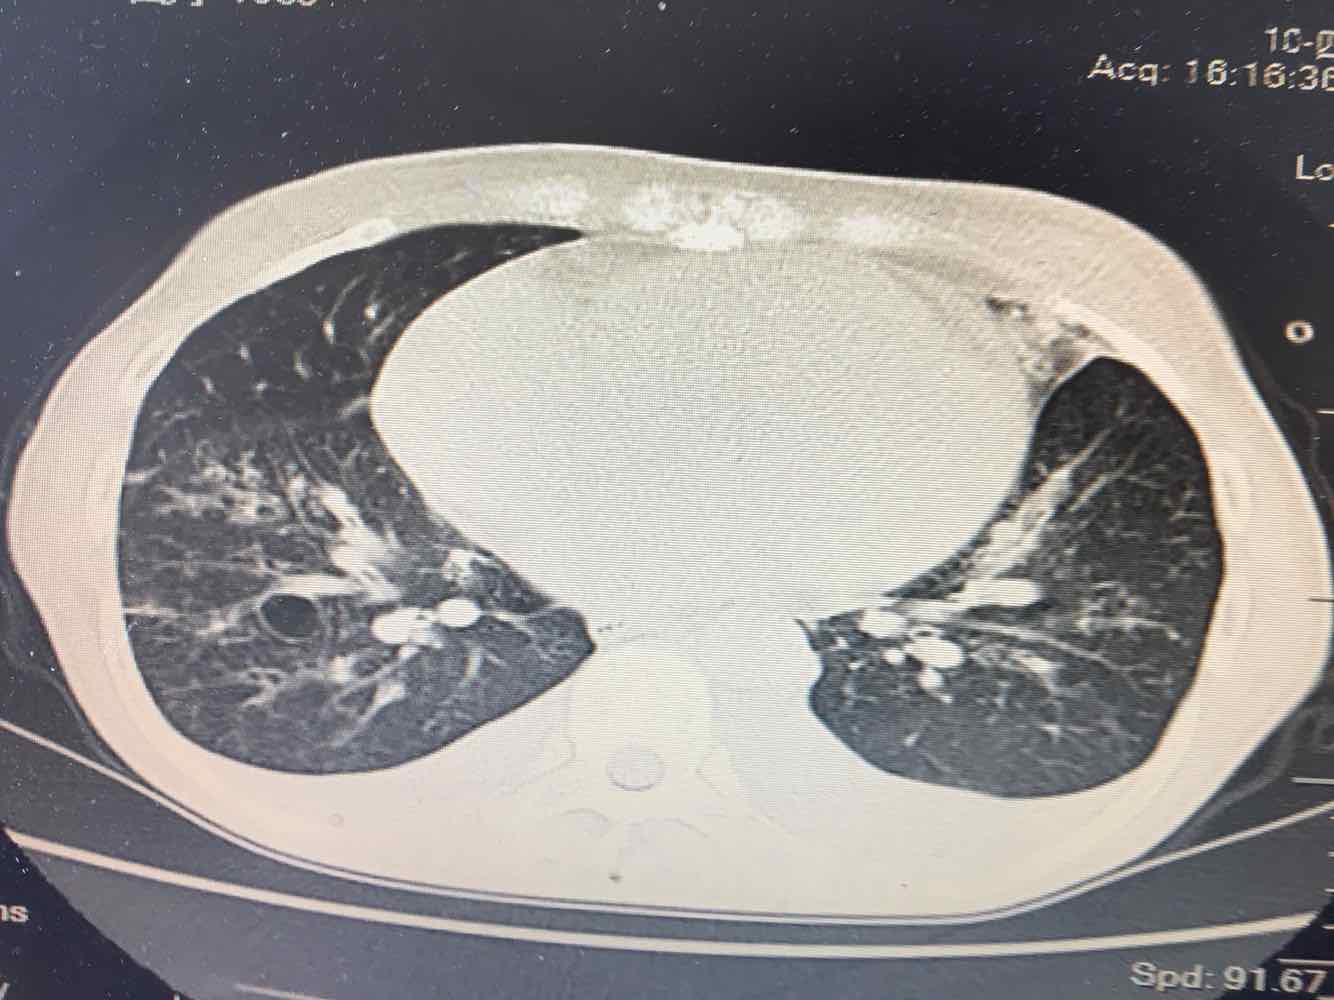

女,51岁,支气管扩张病史多年。慢性咳嗽咳痰喘息30年,加重1个月,无发热,气短为主,痰液不多,上腹不适,少尿。双肺干湿罗音。